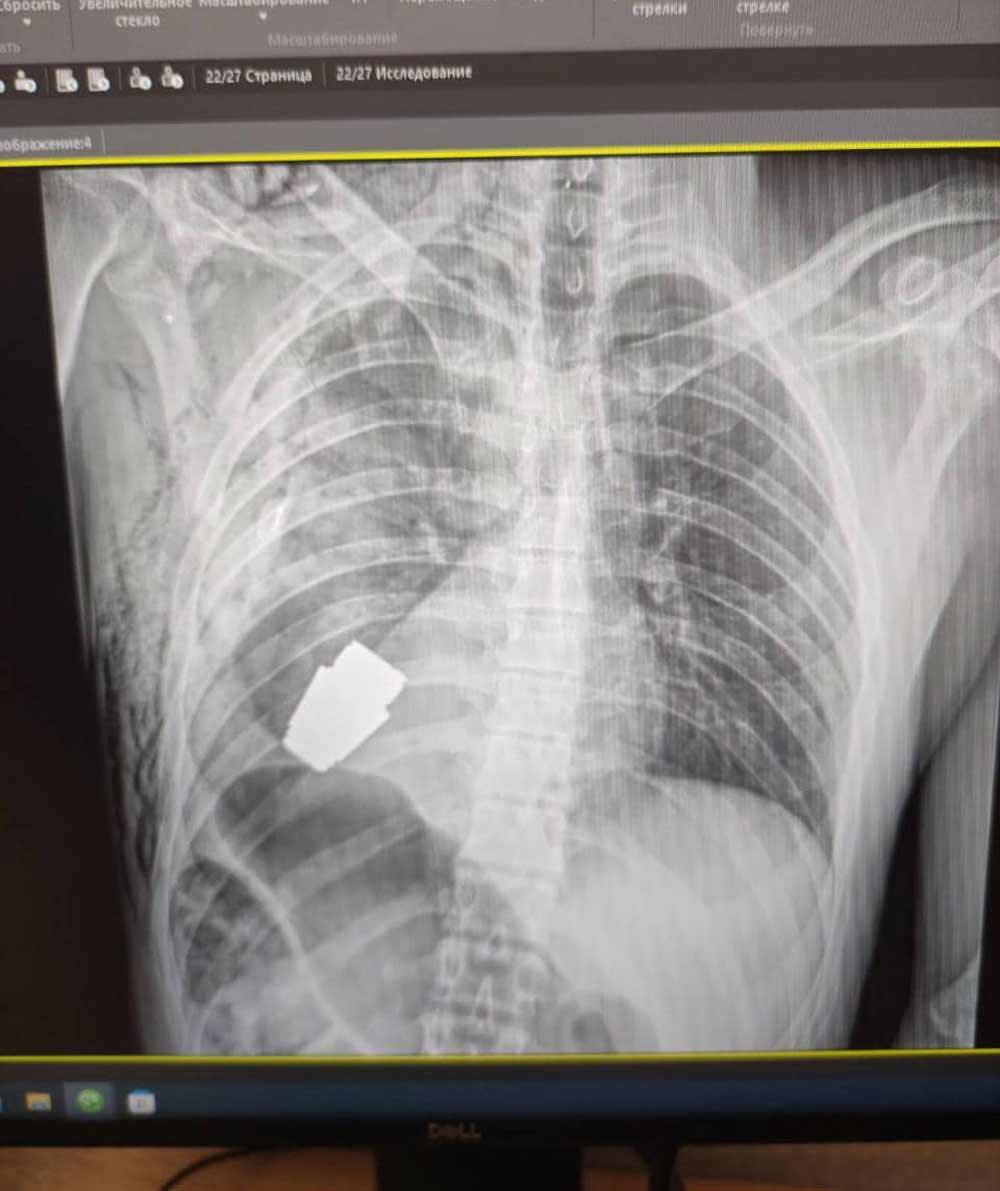

உக்ரேனிய சிப்பாயின் நெஞ்சிலிருந்து வெடிக்காத கிரனேட் அகற்றப்பட்டது

உக்ரேனிய  சிப்பாய் ஒருவரின் நெஞ்சுக்குள்ளிருந்து, வெடிக்காத கிரனேட்   ஒன்றை அந்நாட்டு மருத்துவர்கள் சத்திர­சிகிச்சை மூலம் அகற்றியுள்ளனர். சிப்பாயின் இதயத்துக்கு அருகில் இந்த கிரனேட் சிக்கியிருந்தது.

இந்த கிரனேட்  எந்த வேளையிலும் வெடிக்­கும் அபாயம் இருந்ததால், இரத்தம் வெளியேறுவதை மின்சாரத்தால் கட்டுப்­படுத்துவதை தவிர்த்து இச்சத்திரசிகிச்சை செய்யப்பட்டதாக உக்ரேனிய இராணுவ மருத்துவர்களின் பேஸ்புக் பக்கத்தில் தெரிவிக்கப்பட்டுள்ளது.

உக்ரேனிய பாதுகாப்புப் படைகளின் மிகுந்த அனுபவமுள்ள சத்திரசிகிச்சை நிபுணர் மேஜர் ஜெனரால் அன்ட்றே வேர்பா தலையில் இசத்சத்திரசிகிச்சை மேற்­கொள்ளப்பட்டுள்ளதாகவும் தெரிவிக்கப்­பட்டுள்ளது.

இராணுவப் பொறியியலாளர்கள் இருவரும் சத்திரசிகிச்சை அறையில் பாதுகாப்புக்காக இருந்தனர்.

சிப்பாயின் உடலிலிருந்து அகற்றப்பட்ட கிரனேட் ட் பின்னர் கட்டுப்பாட்டு முறையில் வெடிக்கச் செய்யப்பட்டது.

இந்த கிரனேட்  எவ்வாறு மேற்படி சிப்பாயின் உடலில் புகுந்து என்பது தெரி­விக்கப்படவில்லை.  எனினும், 4 சென்ரி­மீற்றர் நீளமான இந்த கிரனேட் , 400 மீற்றர் தூரத்திலிருந்தும் ஏவப்படக்கூடியது எனத் தெரிவிக்கப்பட்டுள்ளது.